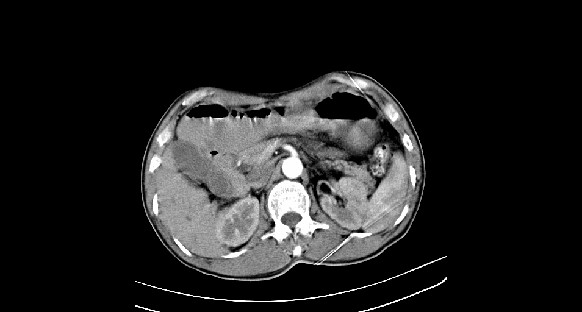

男性,70岁,体检b超发现左肾占位,请各位战友发表一下观点

左肾有两个病灶,且较大的病灶内可见点状钙化灶,增强扫描边缘也是呈渐进性强化,中央部分未见明显强化